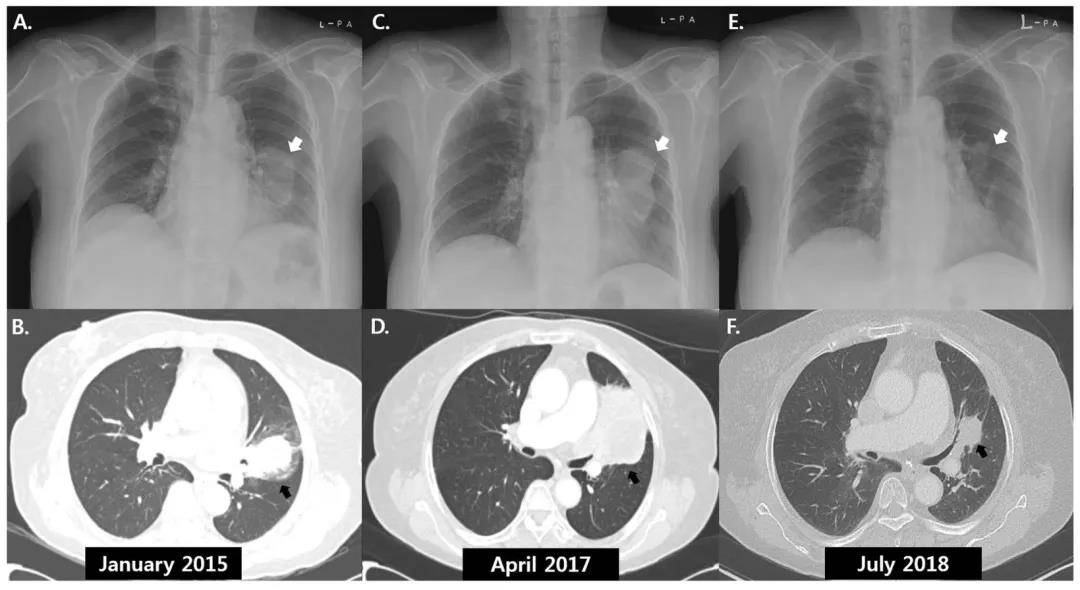

一名非小细胞肺癌患者的影像学资料,图中箭头显示肿瘤神奇地消失了

图片来源:bmcpulmmed.biomedcentral.com